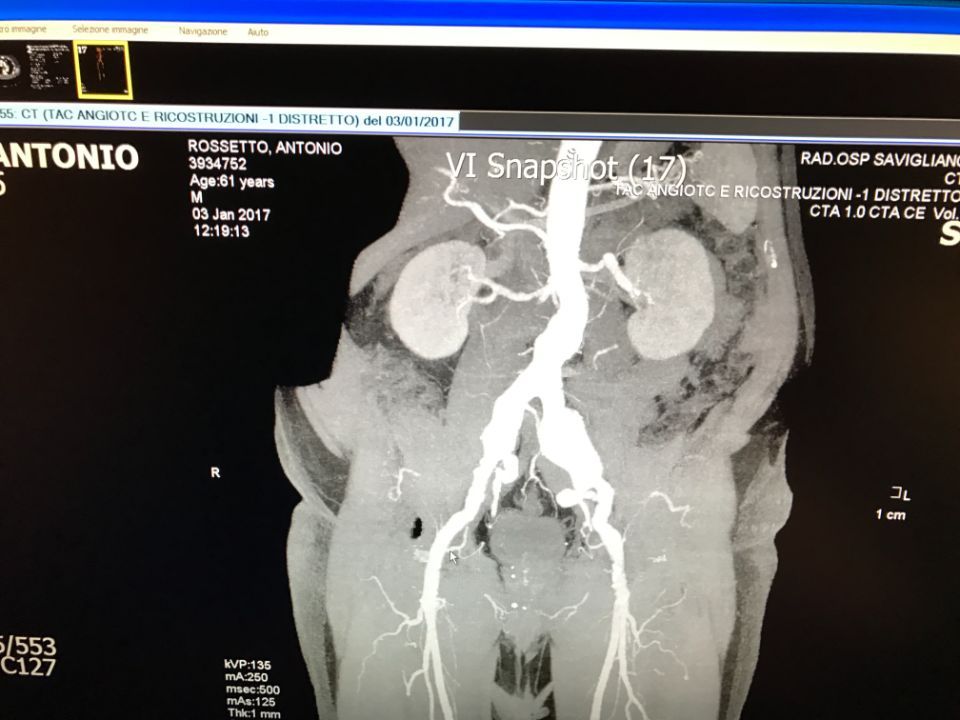

Ecco alcune immagini degli interventi eseguiti dal Dottor Viglione presso il suo studio a Cuneo.